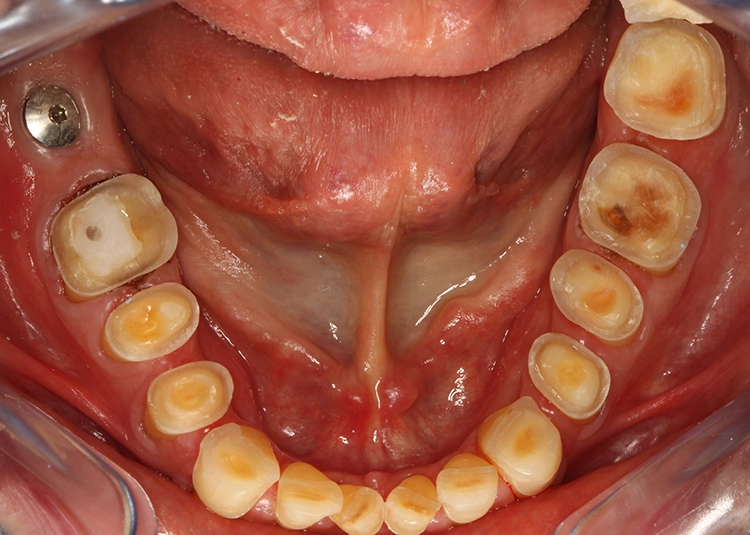

Egger/Wermuth/GrevenRote Ästhetik: Im Ober- und Unterkiefer zeigten sich generalisiert ausgedehnte Rezessionen mit bis zu 8 mm Attachmentverlust vor allem im Bereich der Eckzähne (Miller-Klasse III; Rezessionstyp [RT] 2 [69]. Das Band an keratinisierter Schleimhaut ist durchgehend vorhanden. Die Breite variiert im Eckzahnbereich von 1 mm bis zu 2 mm im Bereich der Unterkieferfrontzähne, der Prämolaren und Molaren (Abb. 1). Die fazialen Rezessionen sind mit approximalem röntgenologischem Attachmentverlust im koronalen Wurzeldrittel (Abb. 2) und Papillenverlust im Bereich zwischen den Kontaktpunkten und der approximalen Schmelz-Zement-Grenze assoziiert (Abb. 1). Der Patient verfügt über eine schmal geformte Oberlippe. Die Lachlinie verläuft mittelhoch (Abb. 3).

Dentalstatus: Es zeigen sich generelle Abrasionen, Attritionen und Erosionen im Ober- und Unterkiefer. Die ursprüngliche anatomische Kauflächenstruktur in den Seitenzahnbereichen ist durch die massiven erosions- und attritionsbedingten Zahnhartsubstanzverluste nicht mehr vorhanden (Tab. 2). Aufgrund der massiven Zahnschmelzverluste erscheint die Zahnfarbe insgesamt gelblicher. Der Patient wünscht sich im Rahmen der Rehabilitation in dieser Frage eine merkliche Verbesserung.

Parodontale Gesundheit bei Attachmentverlust, Bruxismus, Erosion. Abbildung 1 sowie 6 bis 9 zeigen den Anfangsbefund als intraoralen Fotostatus.*